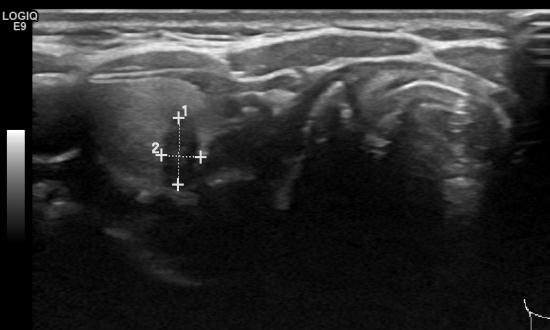

건강검진센타에서 의뢰되신 44세 여자분이시며 갑상선우엽에

0.6cm의 작은 혹이 있어

원 미세침세포검사상 유두상암 진단되셨습니다.